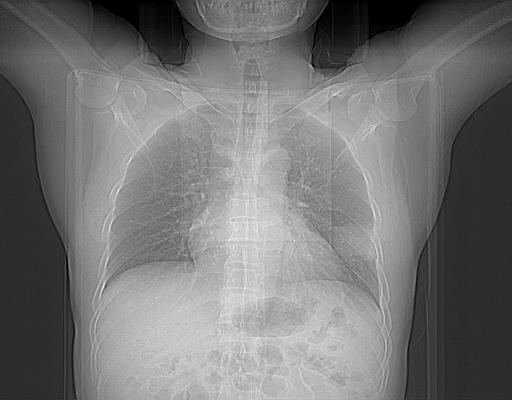

标题: CT21560:胸部肿块影,请会诊 [打印本页]

标题: CT21560:胸部肿块影,请会诊

男,38岁,于2009年8月9日晚突发左侧胸痛,今x线提示左下肺阴影,为了明显确诊断,行ct检查,

血常规:嗜酸性细胞增高,单核细胞增高。